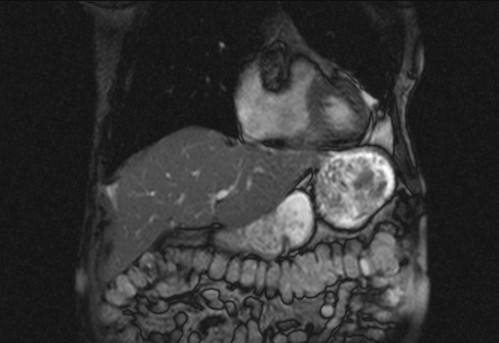

Auffälliges Abdomen bei der Vorsorgeuntersuchung einer älteren Dame

ICD: C64